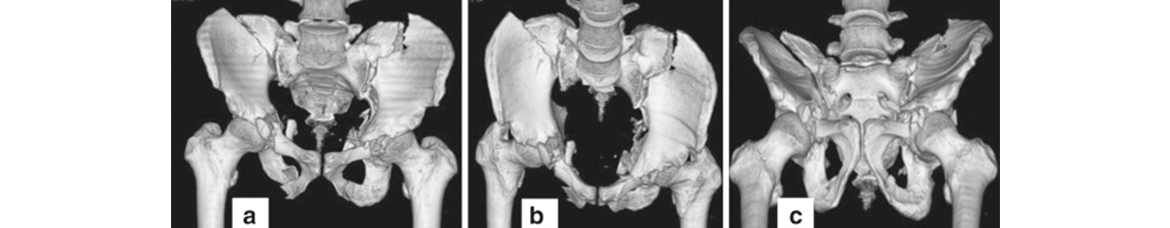

We as a tertiary care centre in the field of orthopaedics encounter a lot of complex trauma with extremely serious injuries around the hip

The injuries encompass hip dislocations with or without ACETABULAR fractures.

These fractures require urgent and precise surgical fixation to achieve the ultimate outcome. We at our centre routinely perform such surgeries.

If left untreated, these injuries can result in gait problems and may lead to painful restriction of movements. Hence to avoid these complications, we offer the expert and accurate advice coupled with definite treatment to deliver the best outcome.